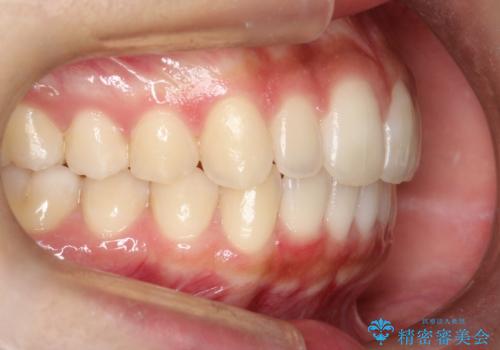

見た目、嚙み合わせ及び、治療期間や施術内容に大変ご満足いただきました。

抜歯は行わず上顎の奥のスペースを利用して歯をスライドする方法の他に歯列弓の拡大やディスキング(歯と歯の間の隙間を作る処置)を行い叢生を改善しました。

歯の大きさの不揃いが原因の正中のズレは、ディスキング量を調整することで合わせています。

上の歯を後ろに送る方法として、歯茎に入れた小さなネジからゴムかけをして歯列全体を後ろに引っ張りました。

矯正装置としてはマウスピースを使用しています。